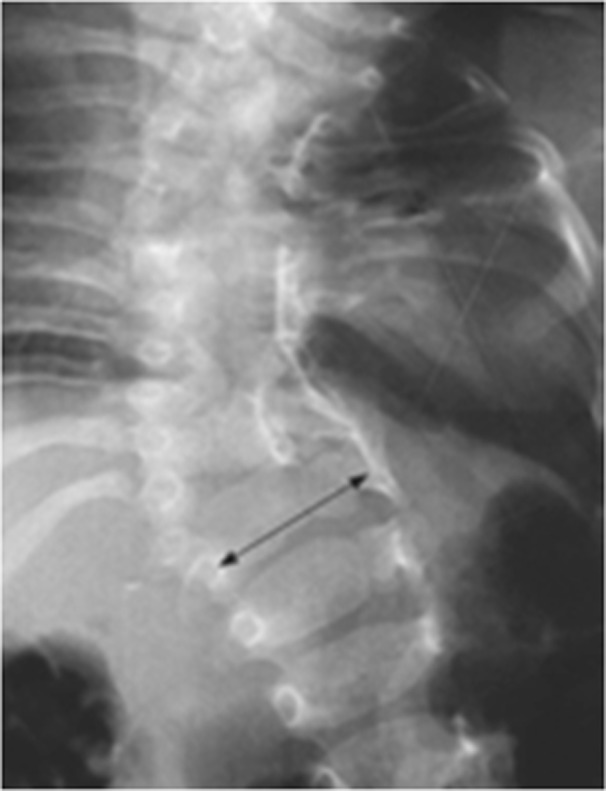

The skin of all the subjects had signs at the region of the back, similar to local hypertrichosis, hemangiomas, or skin dimpling (a representative image is shown in Fig. 2). Widening of the interpedicular distance at the level of one or a few vertebral segments is a very distinctive feature for patients with diastematomyelia as shown in Fig. 3. In such cases, the presence of spinal cord splitting was clearly visualized on MRI (Fig. 4). CT images provided the necessary information to differentiate between bony and fibrotic septum (Fig. 5). In our population, 18 (90%) subjects had different types of congenital vertebral anomalies, including failure of formation, segmentation and a combination of aforementioned, while 17 (85%) subjects had congenital scoliosis. In 2 (10%) subjects with fibrotic septum, there were no congenital abnormalities. The most commonly seen musculoskeletal deformity in subjects with diastematomyelia was lower limb asymmetry. Atrophy with increasing muscle weakness was thought to be a case of neurological deterioration, thus being an indication for surgery. Partial restorations of neurological function were observed in total four subjects, for whom spur resection surgery was carried out.

Fig. 3.

Example of widening of the interpedicular distance on anteroposterior (AP) X-ray in patient with diastematomyelia